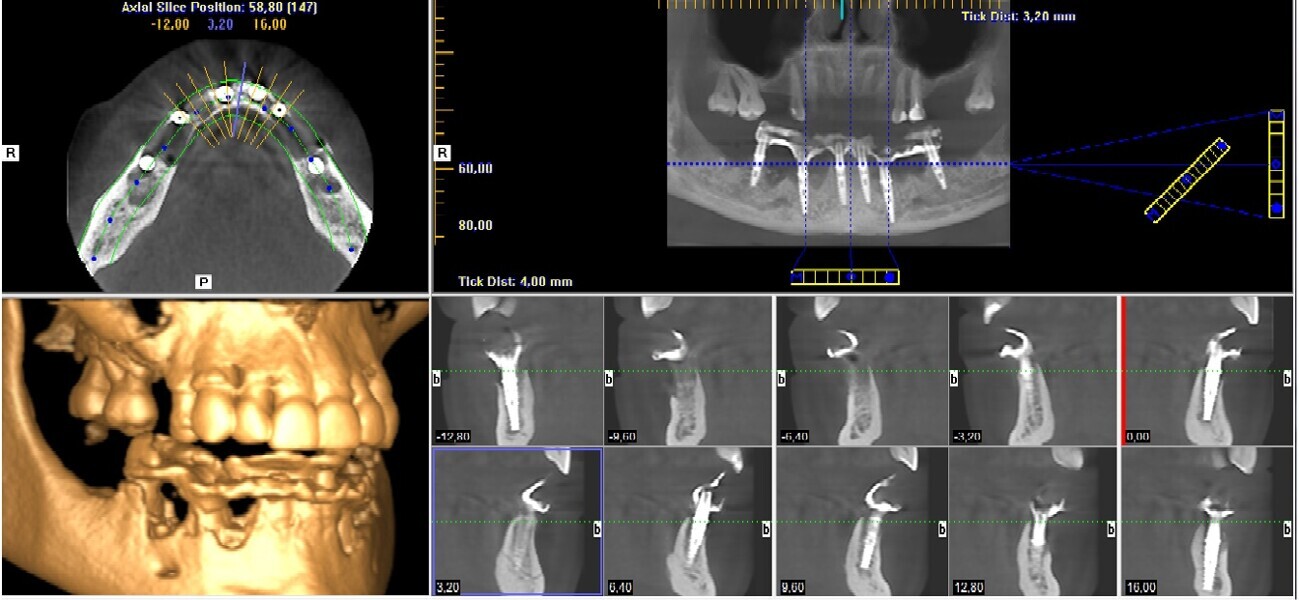

Natychmiastowa implantacja i zaopatrzenie protetyczne pacjentów z zaawansowaną chorobą przyzębia